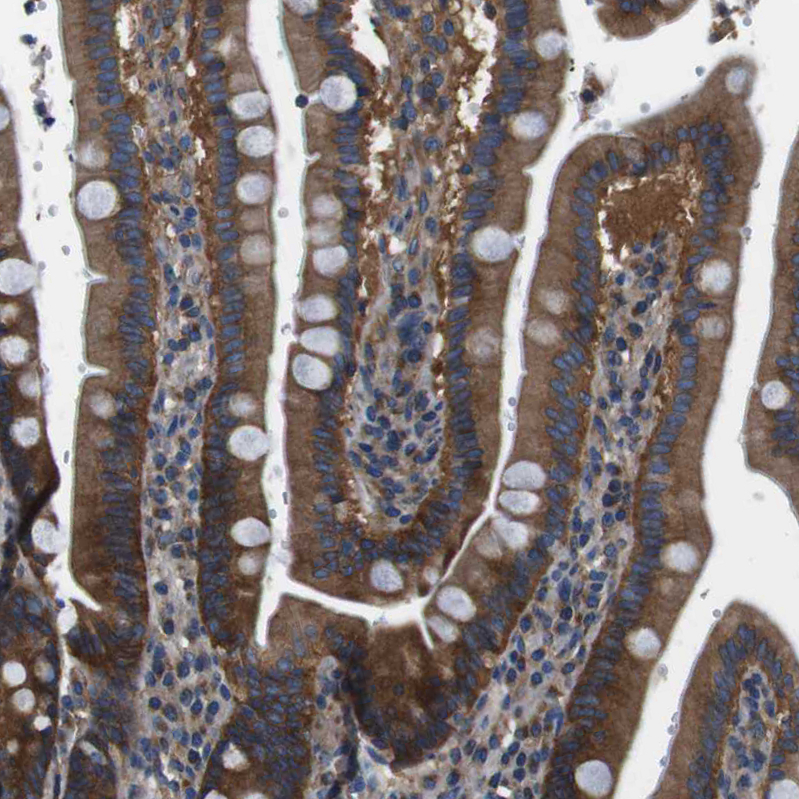

Immunohistochemical staining of human duodenum shows moderate to strong cytoplasmic positivity in glandular cells.